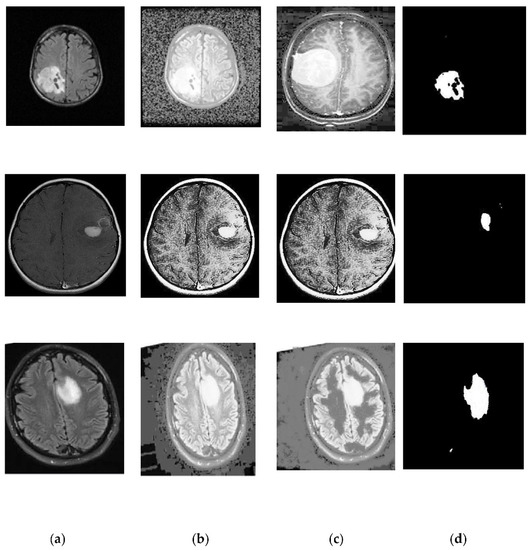

2.2. Preprocessing: Image Enhancement

- Using additive wavelet transform, the image ‘I’ is separated into three sub-bands: s1, s2, and s3.

- The tiling procedure is carried out in sub-bands s1 and s2.

- After that, the ridgelet transform is applied to each of the tiling sub bands s1 and s2.

2.3. Segmentation